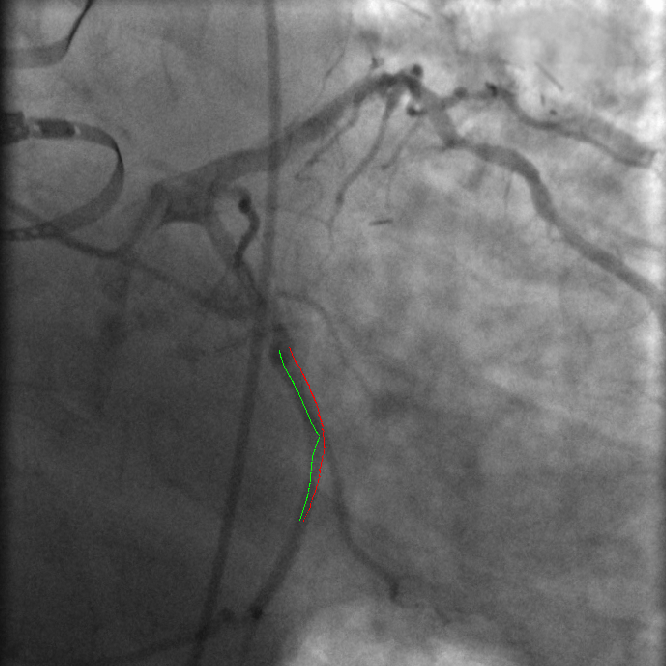

Figure 1: VOIDD: (from left to right)Input image f𝑓f; centerline of segmented guidewire tip; tip candidate (red) matched to vessel centerline (green) marked by pairings(blue); corresponding location (green) of guidewire tip(red) inside vessel.

The main contribution of this article is the proposition and the assessment of a method, called VOIDD, to automatically detect the so-called vessel-of-intervention during the navigation of the guidewire. More precisely this algorithm is able to recognize from the stream of fluoroscopic images following the acquisition of the reference sequence, the period corresponding to the guidewire navigation and to exploit it to determine the vessel-of-intervention (see Fig. 1). In order to reach this goal a general tracking algorithm is proposed and explained in section 2.1. This algorithm relies on features extracted from the navigation and reference images. Various methods can be adopted or designed to extract these features to be used with our general tracking algorithm. In this article, these features consists of vessel tree segmentation and of guidewire tip location candidates detection with advanced approaches involving the use of min tree [9]. Graph-based matching approaches derived from [2] are used to match the guidewire tip with the vessel. These developments have been evaluated on 4 patient dataset. We present an evaluation methodology which characterizes the correctness of the guide wire tip detection and the correct identification of the vessel navigated during the procedures. On a dataset of 4 patients, VOIDD identifies vessel-of-intervention with accuracy in the range of 88%percent8888\% or above and absence of tip with accuracy in range of 98%percent9898\% or above depending on the test case.

Tip candidate extraction. Guidewire tip appears as contrasted thin and elongated object in the fluoroscopic image. We are interested to segment the guidewire tip, using a component tree called min tree. The min tree [9] structures all the connected components of the lower-level sets of the grayscale image based on inclusion relationship. We assign to any connected component C𝐶C of the min tree \mathcal{M}, a shape attribute characterizing the shape and structural properties of guidewire tip. Then, the considered attribute 𝒜𝒜\mathcal{A} describes the elongation of the components. For any component C𝐶C𝒜(C)=(π×lmax(C)2)/|C|,𝒜𝐶𝜋subscript𝑙𝑚𝑎𝑥superscript𝐶2𝐶\mathcal{A}(C)={(\pi\times{l_{max}(C)}^{2})}/{|C|}\enspace, where |.||.| represents cardinality and lmax(C)subscript𝑙𝑚𝑎𝑥𝐶l_{max}(C) is the length of the largest axis of the best fitting ellipse for the connected component C𝐶C. Since the guidewire tip is thin and long, the component corresponding to the tip have high value of attribute 𝒜𝒜\mathcal{A}. A mere thresholding of the elongation 𝒜𝒜\mathcal{A} is not sufficient, often giving other long and elongated (unwanted) objects like pacing lead and filled catheters. Indeed, these objects have higher elongation value than the guidewire tip. Hence, according to physical properties of the guidewire tip, we set a upper bound value tmaxsubscript𝑡𝑚𝑎𝑥t_{max} on 𝒜𝒜\mathcal{A} to maximum possible elongation value of the guidewire tip, to ensure that extracted components contain guidewire tip. Even with this upperbound threshold keeping the most elongated component does not always lead to the desired tip. Based on min tree structure, the nested connected components that satisfy the criterion are filtered to preserve the component with largest area (taking aid of the inclusion relationship). Therefore, we adopt the shaping framework [10] that allows us to efficiently extract significant connected components. The extracted components constitute the tip candidates. Shaping extensively uses the min tree structure to regularize the attributes and to select the relevant components. In order to facilitate matching, we perform skeletonization [3] of the selected connected component(s) to obtain centerline of the tip candidates. Fig. 1 shows the obtained centerline of segmented guidewire tip from the input image. This centerline of the tip candidate 𝒞𝒞\mathcal{C} is modeled as a discrete polygonal curve.